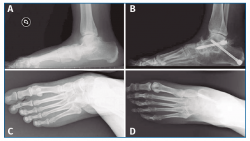

No se pudo realizar una valoración completa del resultado de la corrección clínica por no disponer de fotografías pre- y postoperatorias de todos los pacientes (Figura 5), aunque, como hemos comentado anteriormente, se valoró la evolución radiológica en la totalidad de los pacientes (Figura 6).

Figura 5. Aspecto clínico pre- (A y C) y postoperatorio (B y D) mostrando la corrección del valgo del pie izquierdo, así como la convexidad de la cara medial y el hundimiento del arco interno.